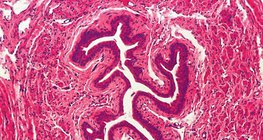

Its speed depends on the thickness of the myelin sheath.